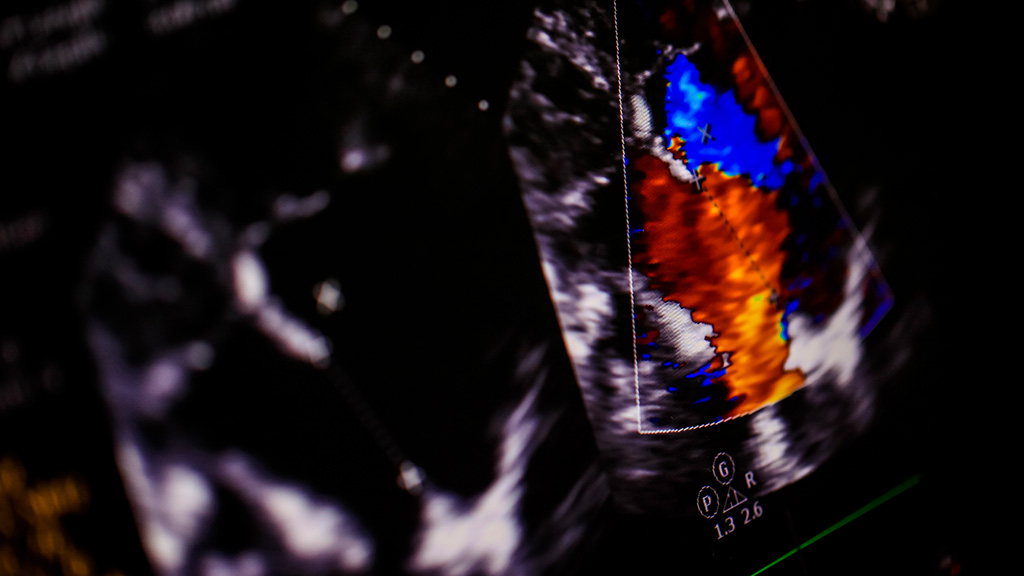

Ultrasonido Doppler Color Renal